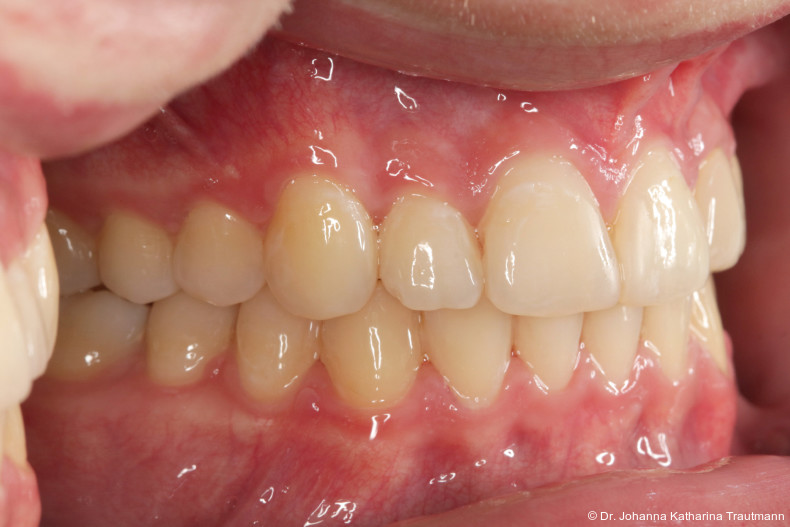

Zur objektiven Quantifizierung des Behand lungsergebnisses wurde der Peer Assess ment Rating(PAR)Index erhoben.23 Im vorliegenden Fall konnte der PAR-Wert von 25 auf zwei reduziert werden, was einer Verbes serung von 92 Prozent entspricht und als hoch wertiges okklusales Ergebnis einzustufen ist.24 Zur Vorhersage der Langzeitstabilität bei Spalterkrankungen lässt sich dieser Fall in die Gruppe 1 des GOSLON Yardstick Index ein ordnen. Dieser sagt eine exzellente Langzeitstabilität vorher.25 Auch der Patient zeigte sich mit dem Ergebnis sehr zufrieden. Während der anderthalbjährigen Retentionsphase erfolgte zusätzlich eine ästhetische Nasenkorrektur zur Aufrichtung des linken Nasenflügels, wodurch neben der dentalen auch die extraorale Rehabilitation erfolgreich abgeschlossen werden konnte.